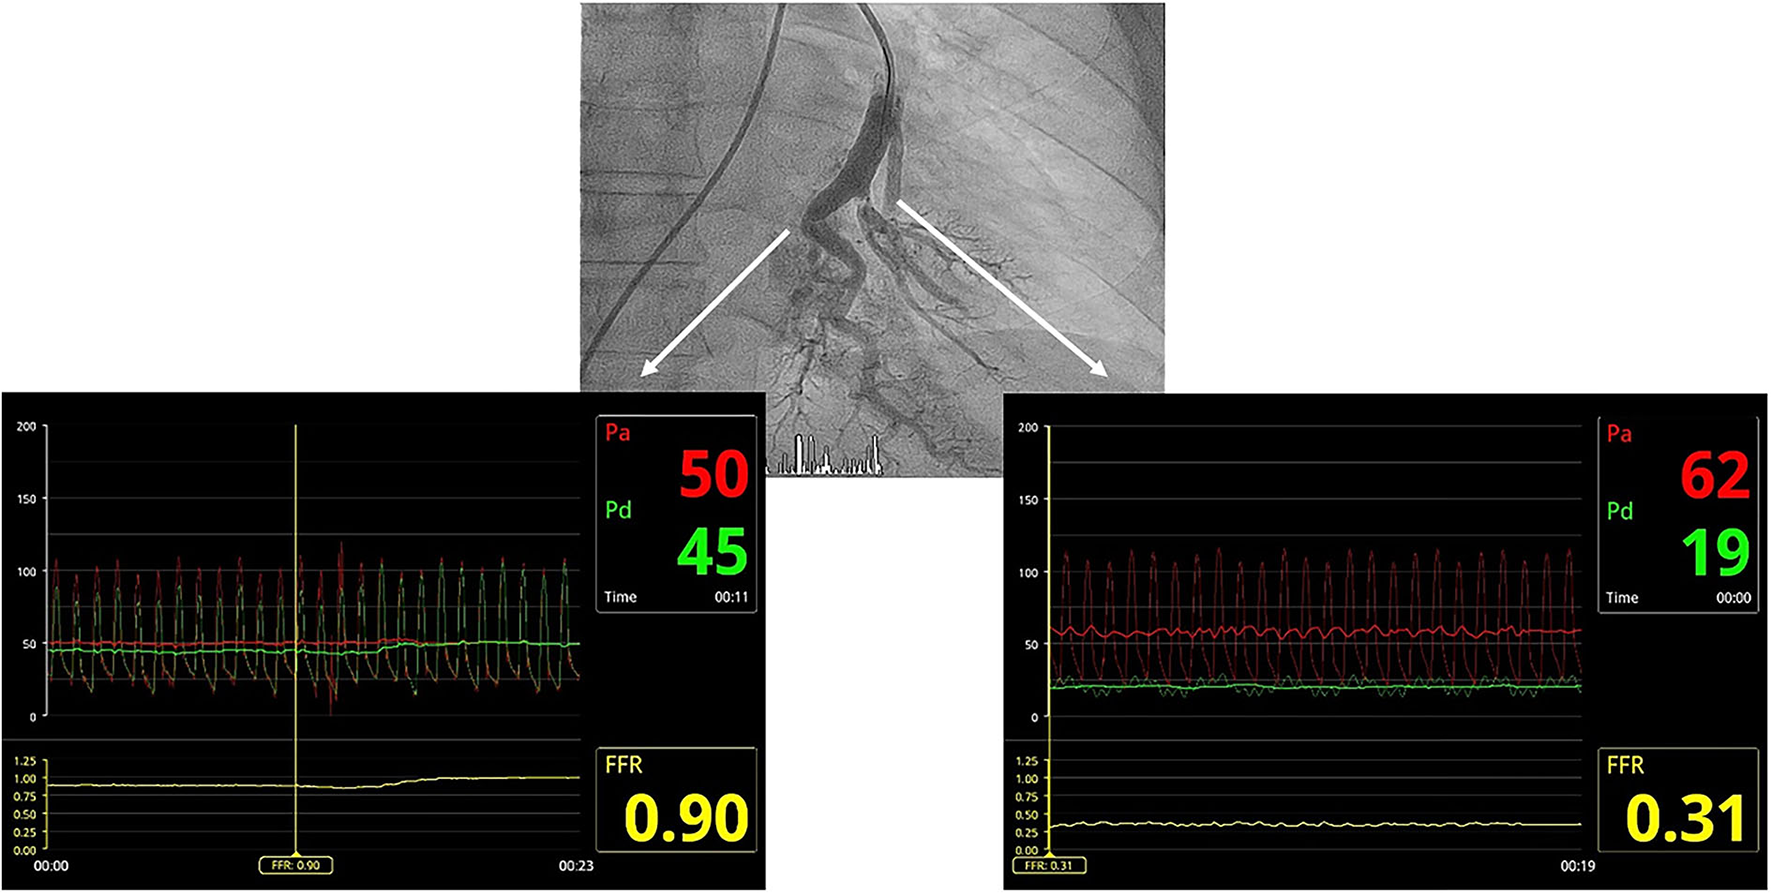

Figure 1

Utility of the pressure wire in clarifying angiographic images corresponding to arterial branch bends or true webs. The radiolucent image in the segmental branch on the left of the composition corresponds to an artery loop, with no significant pressure gradient between the guide catheter and the pressure wire distal to the lesion. The radiolucent image in the segmental branch on the right corresponds to a real web, with a significant pressure gradient between the guiding catheter and the pressure wire distal to the lesion, which is significantly damped.